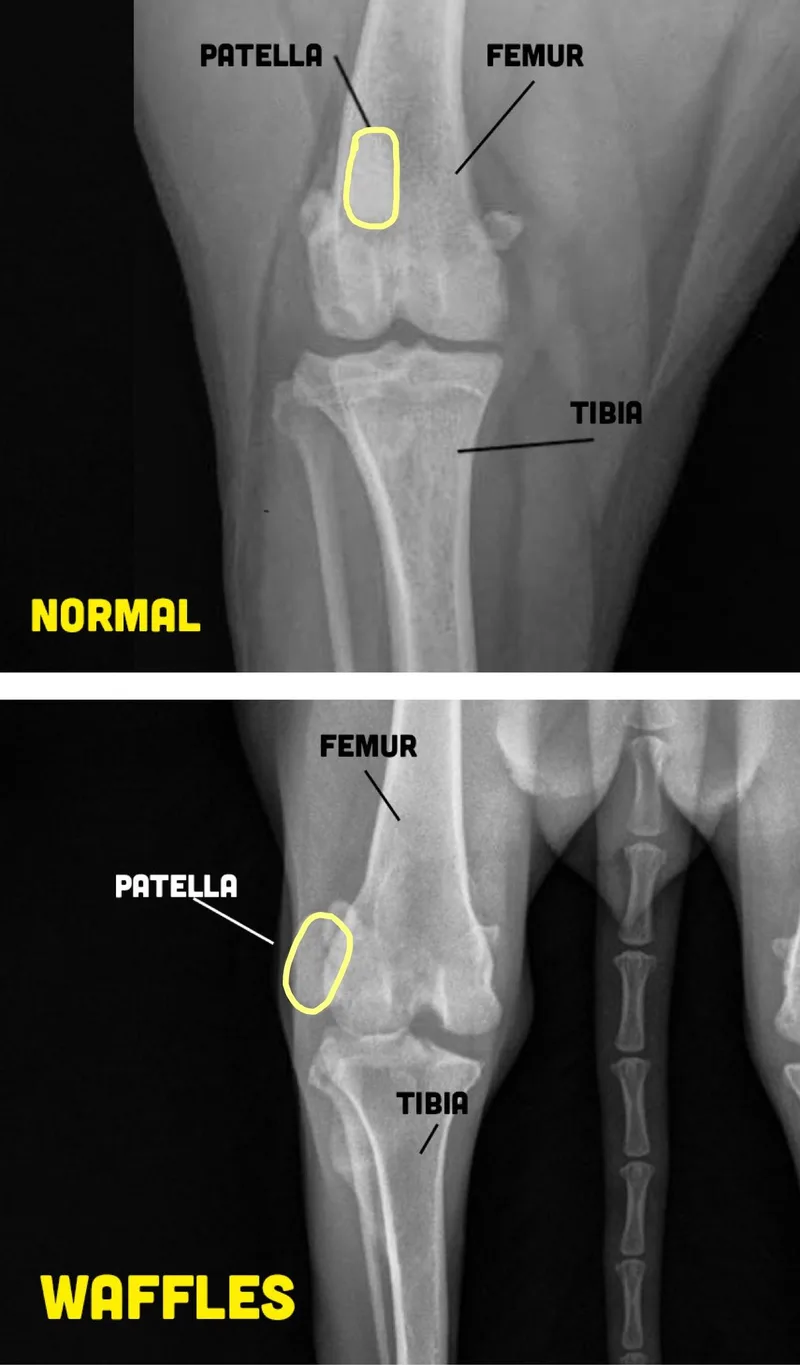

Waffles landed at Arizona Humane Society after being found as a stray. It was very clear that she had mobility issues with her hind limbs, and needed medical attention. AHS learned that Waffles had severe patellar luxations that caused a painful, hunched walk and visible difficulty getting around. After deciding that Waffles’ condition was too severe for them to perform surgery, she was placed on the E-list. Waffles urgently needed rescue and medical care, and we are so grateful to have found a foster who stepped up for this petite 3 year old girl, giving her the chance she deserved. After looking closer at her medical records, we also learned that she had 2 BB pellets near her spine adding to concerns about her overall condition. Despite everything she had been through, Waffles remained incredibly sweet and friendly, just needing a little time to warm up to new people. Waffles entered foster care in August and had corrective surgery on both knees in September. Recovery has not been her favorite thing, but she has had an incredibly patient foster (and a lot of treats!) to get her through. After just three months of recovery, she is now walking so much better and enjoying life in her foster home! Waffles adjusted well to her foster home, even with surgery and recovery happening shortly after arrival. Now that she’s healed, her personality is really shining — she’s a happy, playful, high-energy girl who loves being part of the action. She enjoys playing with other large dogs, is very affectionate once she knows you, and responds well to verbal correction and redirection. Like many young, energetic pups, she can get into mischief if bored (counter surfing is her fave), and she does have some separation anxiety, so continued structure and enrichment will be important. She hasn’t had a ton of walking experience yet due to recovery, but now that she’s past that phase, she’s ready to start exploring the world one paw at a time! Waffles would do well in a wide variety of homes and is a pretty adaptable girl overall. She could thrive with both a young or older household, or even a family with children ages 3 and up. She also enjoys the company of other young or playful dogs and would love a canine buddy to romp around with. Whether her future home is quiet or busy, she is ready to enjoy her fully healed, happy life. Waffles is ready to serve up some unconditional love in her forever home — no syrup required! https://azhuskyrescue.com/adoption-application/